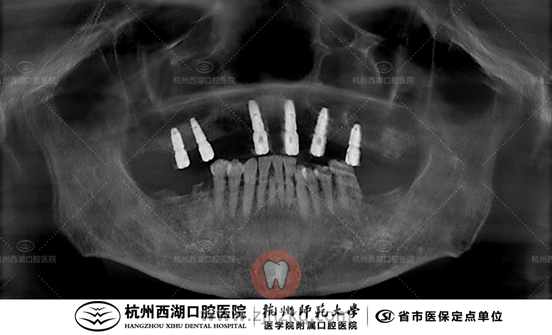

术前CBCT照如下

检查:龋齿 根尖炎

医生建议:下颌拔除,All-on-6即刻负重